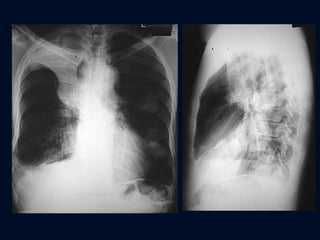

ATELECTASIA LÓBULO SUPERIOR IZQUIERDO Desplazamiento cisura mayor adelante, paralelo a la pared torácica Opacidad lineal ancha, paralela a la pared anterior TAC apariencia triangular con punta hacia la superficie anterior del tórax

ATELECTASIA LÓBULO SUPERIOR IZQUIERDO